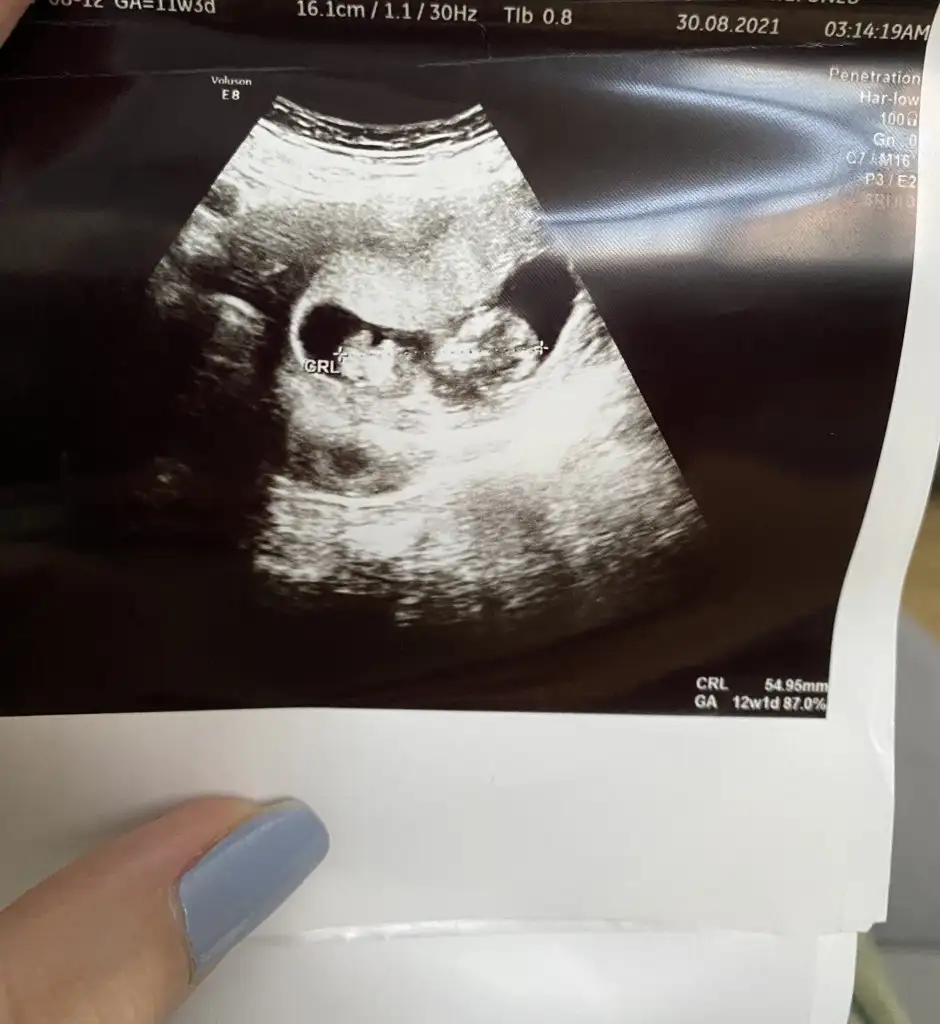

12 haftalık doktor kız gibi dedi ama yanılma çok oluyor dedi 1 ay sonra netleştirirz dedi bazen pipilerini göremiyoruz dedi çok ufak olduğu için yanılabilriz dedi